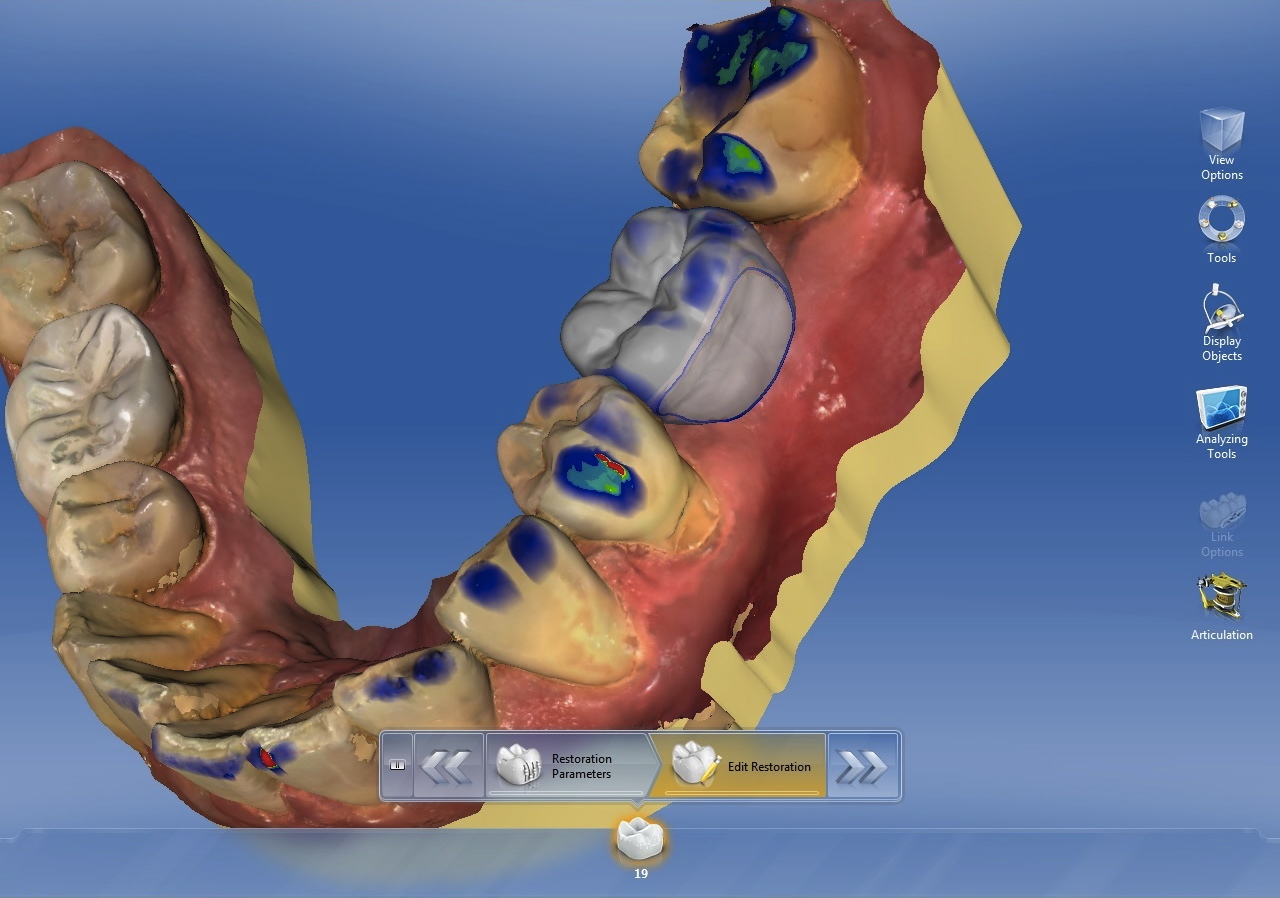

The implant is allowed to integrate, during which time the final restoration is designed. Ceramic screw-retained crowns are the restoration of choice for the SAFE implant protocol because they allow for tissue contouring and are esthetic. Besides being retrievable, they also eliminate cement sepsis caused by subgingival cement, a leading cause of post-restorative implant failure.25

Ivoclar Vivadent (www.ivoclarvivadent.com) makes an IPS e.max® abutment block with a pre-milled screw access hole that fits precisely over a Sirona TiBase. Sirona also makes an inCoris Meso block that is a zirconia block with the same pre-milled hole. There are other companies that make TiBase abutments, but they are not manufactured to fit the Ivoclar or Sirona blocks. In the author’s opinion, these materials simplify the fabrication process of screw-retained implant crowns. Once designed and milled, the restoration is processed in a porcelain furnace and bonded to the TiBase with an appropriate cement (Figure 6). If chairside CAD/CAM is not available, a fixture-level PVS impression is taken after integration is confirmed and sent to a lab for fabrication of the final restoration.

Assembled screw-retained crown.

Figure 6